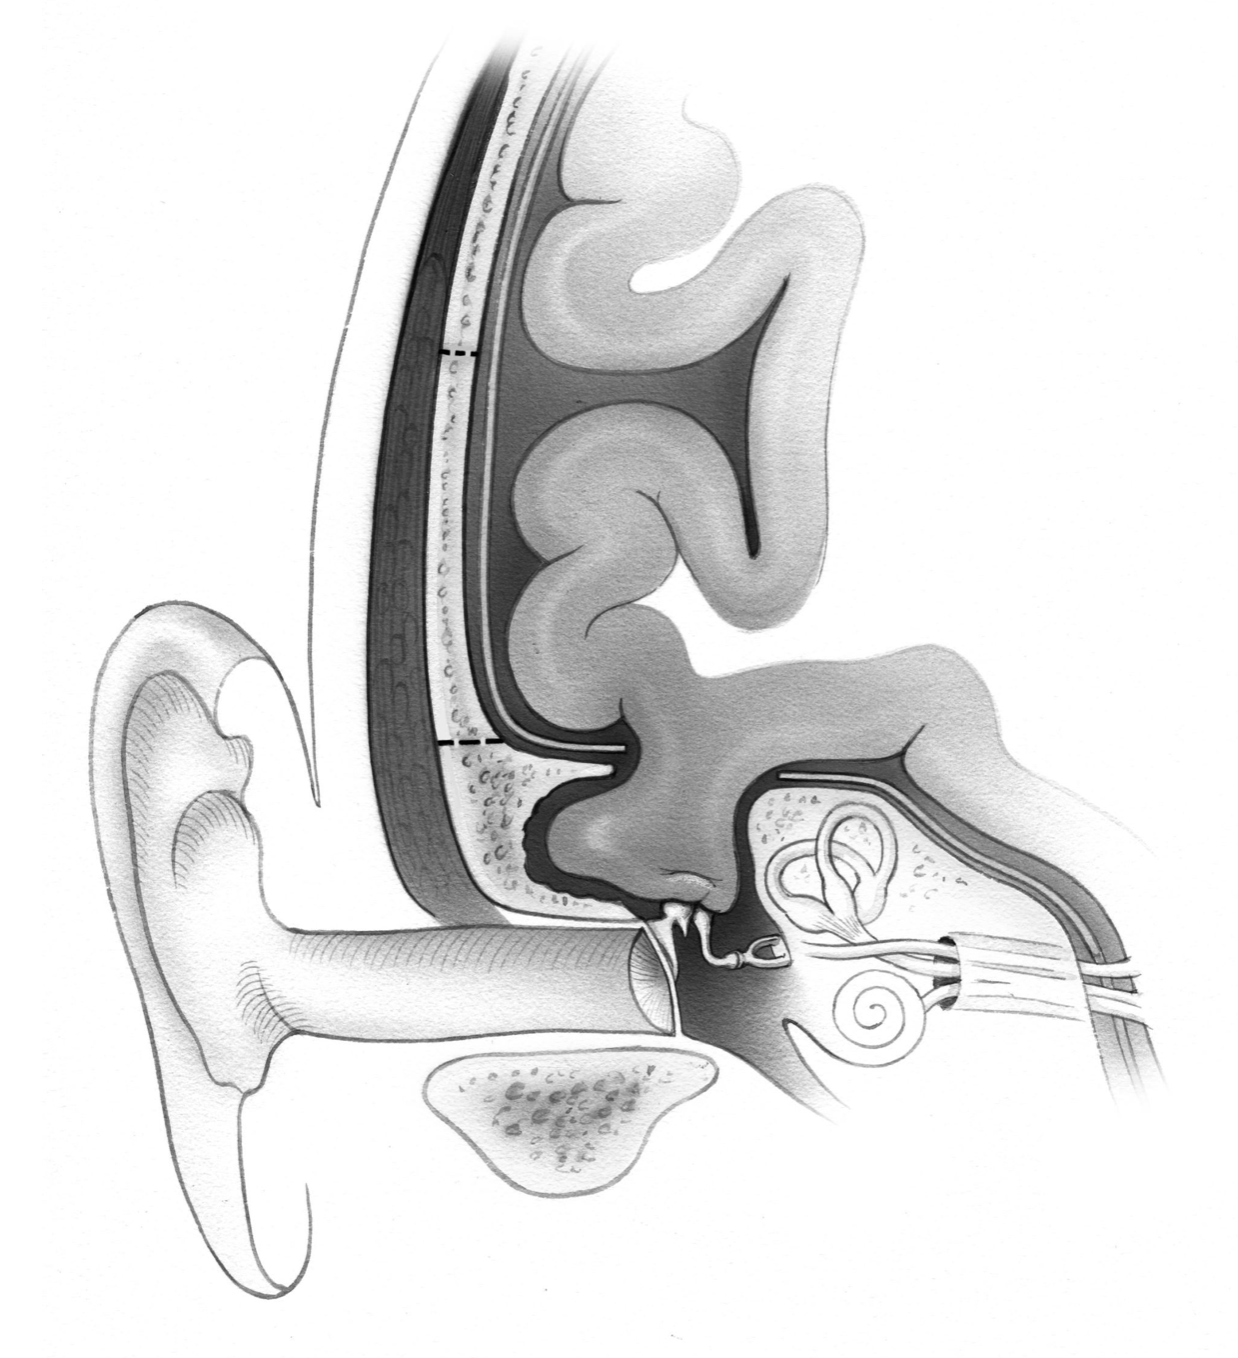

Advanced otology encompasses complex ear and skull base conditions requiring specialized surgical care. We offer cochlear implants and bone conduction implants for hearing loss, treat acoustic neuroma and temporal bone tumors, and perform stapes surgery for otosclerosis. Our team also manages cholesteatoma, superior canal dehiscence, and other advanced ear conditions. Select a topic below to learn more.